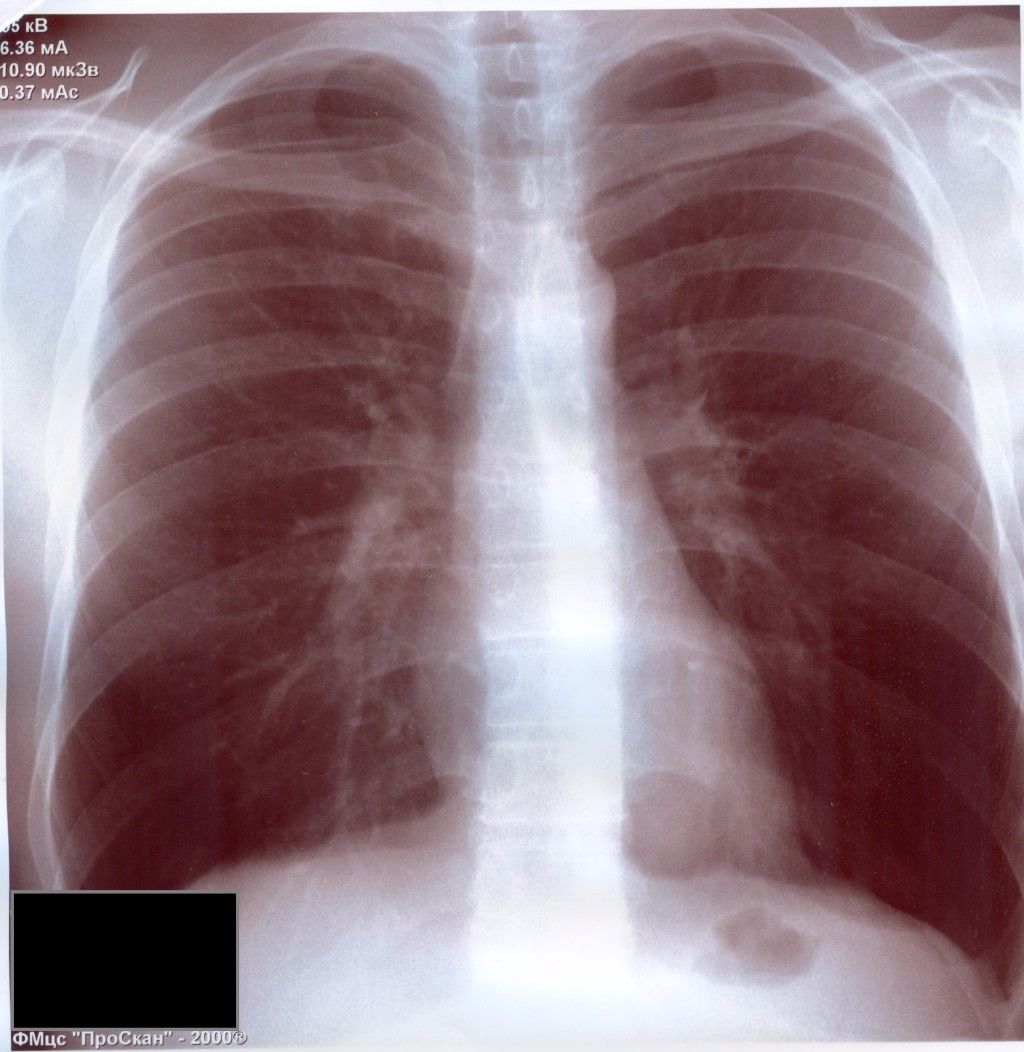

Рентген здоровых легких: примеры снимков и советы